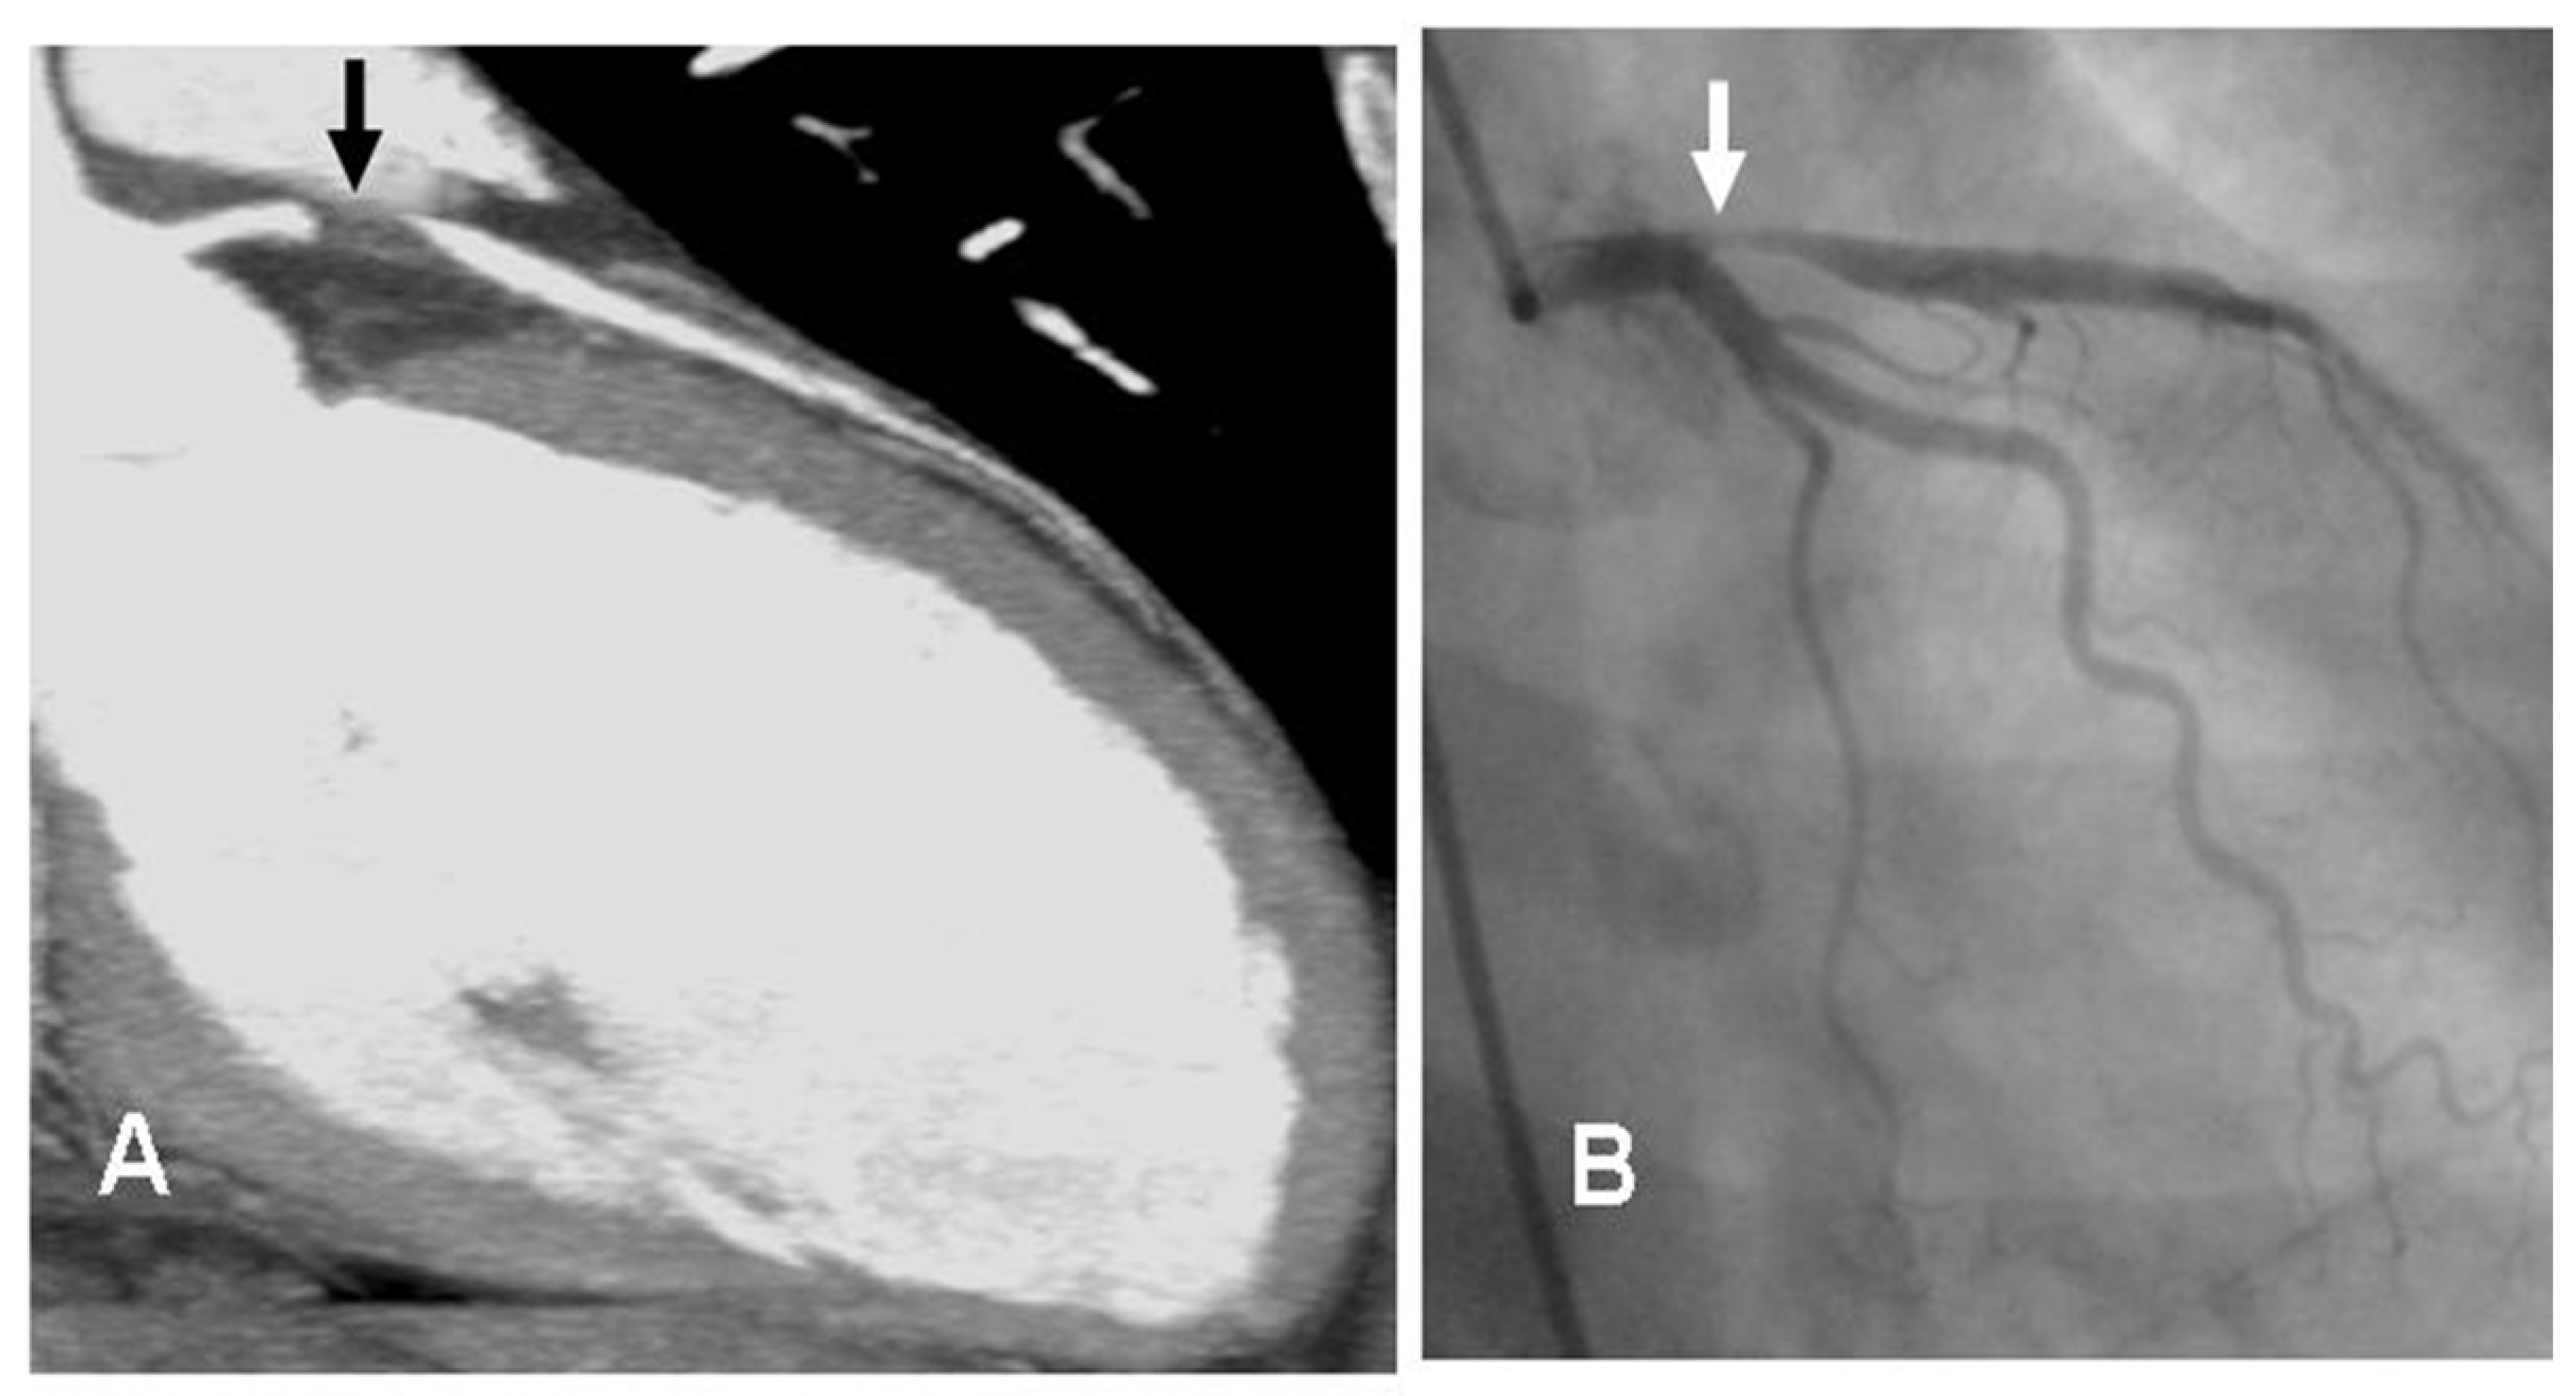

Shaw et al. [60] reported that obstructive CAD was less prevalent in women than men (46% vs. 72%) and mortality was related to the number of stenosed vessels. Due mainly to the smaller diameter of coronary arteries in women, in spite of the overall high diagnostic accuracy for the detection of stable CAD, the sensitivity and specificity of CCTA is slightly lower in women than in men [41,61]. Figure 1 shows an example of a female patient with an acute coronary syndrome (ACS) and a 99% stenosis of the left anterior descendent artery on the CCTA.

Figure 1.

Comparison between CCTA and invasive angiography. Legend: Female, 52 y.o. who presents to the emergency room complaining of chest pain (not typical). At the ECG: ST elevation in precordial leads. Image (A) shows the stenosis of proximal segment of the left anterior descendent coronary artery (LAD), 99% of stenosis (black arrow). The patient was sent to the Interventional Cardiology Department (see invasive angiography in image (B)), the LAD lesion was confirmed (white arrow), and a stent was implanted. ECG: electrocardiogram. Image courtesy of Dr. Luis R. Llerena Rojas, Institute of Cardiology, Havana, Cuba.